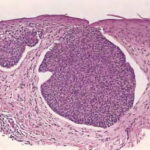

Nodular Basal Cell Carcinoma

Nodular BCCs account for half of all BCCs and are characterized by nodules of large basophilic cells and stromal retraction . The term micronodular BCC is used to describe tumors with multiple microscopic nodules smaller than 15µm .